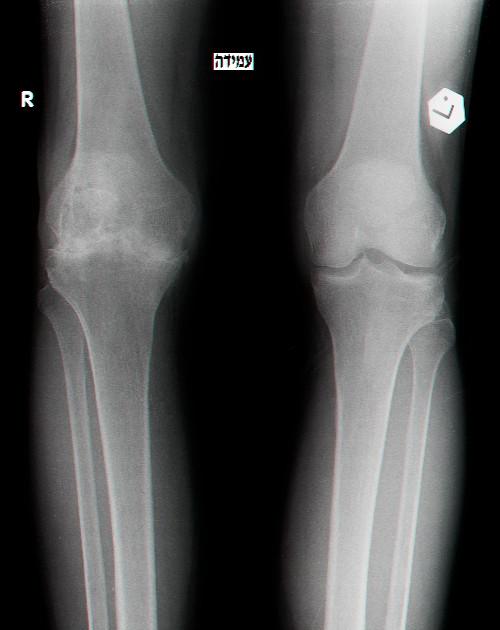

משמאל התמונה צילום רנטגן של ברך ימנית הרוסה לאחר דימומים חוזרים ונישנים, מימין-ברך שמאלית במצב תקין

אותם ברכיים לאחר 15 שנים. שים לב שהסחוס בברך הימנית נשחק באופן קשה-החולה סובל מכאב בכל תנועה של הברך